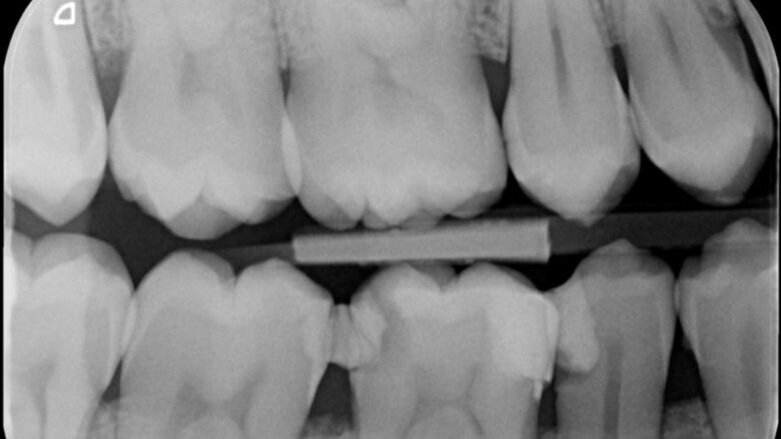

Vier jaar geleden meldde zich een patiënt in onze praktijk met heftige pijn in de regio 46. Na een blik op de bitewing en op de apicale röntgenopname (afbeelding 1 en 2) is de indicatie endodontische behandeling 46 snel gesteld.

Wat mij vooral opviel was de teleurstellende restauratieve begin situatie (46m+d en 45d).

Zeker in een verdere gave dentitie!

Heftige pijn in deze regio is zeker verklaarbaar.

Maar was er al sprake van een irreversibel proces?

Was goed restauratief ingrijpen op zowel 46 als 45 misschien al voldoende geweest?

Differentiaal diagnose pulpitis 45, (bij opname 5 is de 45 inderdaad ook endodontisch behandeld!)